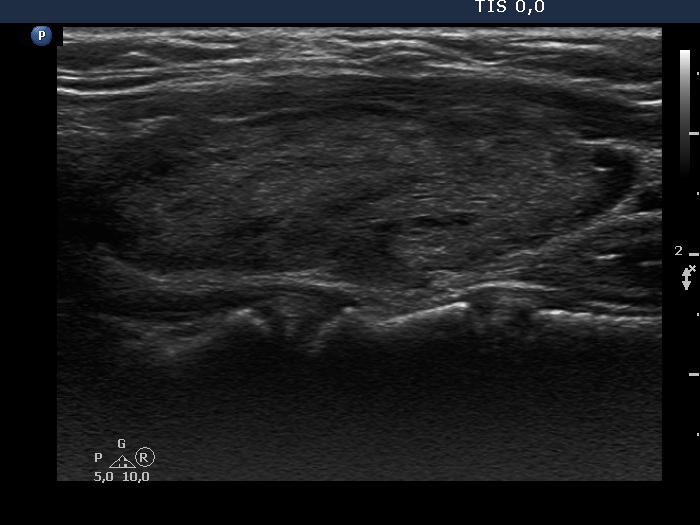

Consecutive patients with the final diagnosis of Hashimoto's thyroiditis - case 18 (1416) (ultrasonographic picture 6)

Left lobe, longitudinal scan.